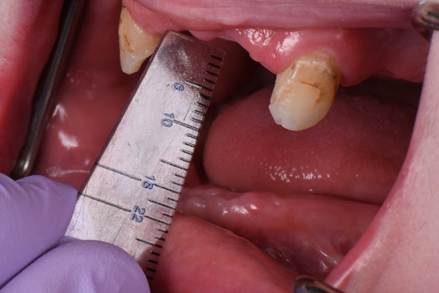

Two months later, the full prosthodontic evaluation revealed severely limited opening with an inter arch maximum distance of around 18mm (from alveolar ridge to ridge) (Fig. 2A and 2B). The maxillary tuberosities were 2mm superior to the retromolar pads bilaterally. The goal of maintaining the cuspids served as a reference during the mandibular repositioning and subsequent use as a potential abutment for future overdenture treatment.

Figure 2B: Intraoral photo at the patients maximum mouth opening